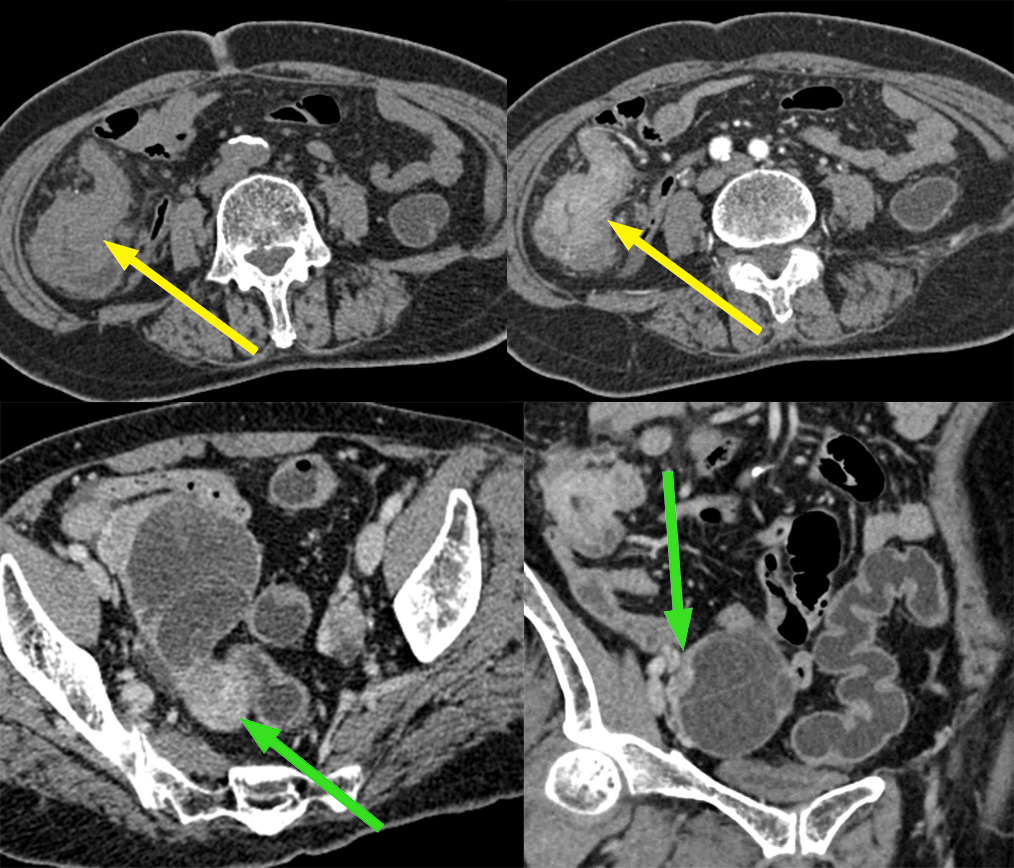

患者,女,70 岁,因排便习惯改变 1 年入院,肠镜及病理:升结肠近回盲部中低分化腺癌;CA125 正常。

影像描述:回盲部肠壁限局性环状增厚,突向腔内,表面不光滑,管腔明显变窄,浆膜层毛糙,增强呈明显不均匀强化,与肠壁边界不清,与周围组织分界尚清,周围脂肪间隙密度增高、浑浊,可见多个结节状软组织密度影,大小约 0.4-1.3 cm,明显强化。右侧附件区见较大囊实性团块影,其内可见分隔,大小约 6.7X5.5 cm,增强扫描实性部分及分隔可见明显强化,与邻近肠管及子宫体分界略欠清。

3、卵巢转移瘤 CT 表现:CT 是鉴别诊断的重要手段,双侧或单侧卵巢实性(乳腺癌,小)或囊实性(结肠癌,大)肿块,80% 的卵巢转移瘤为双侧生长,密度不均,大小不等,常有大量腹水和其他部位转移。

胃黏液腺癌双侧卵巢转移:双侧卵巢多房肿块